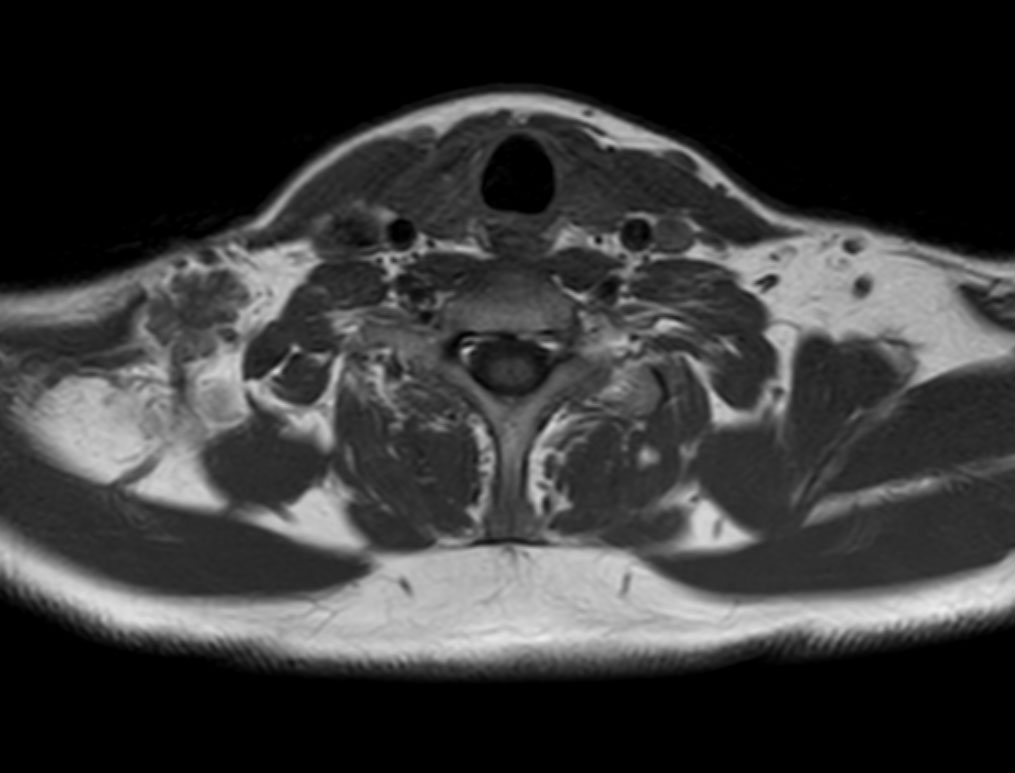

Axial T1w TSE